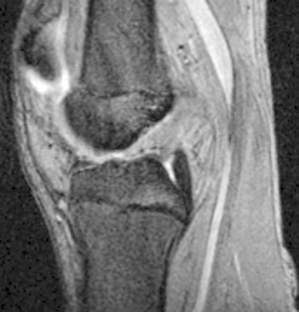

Fig. 5